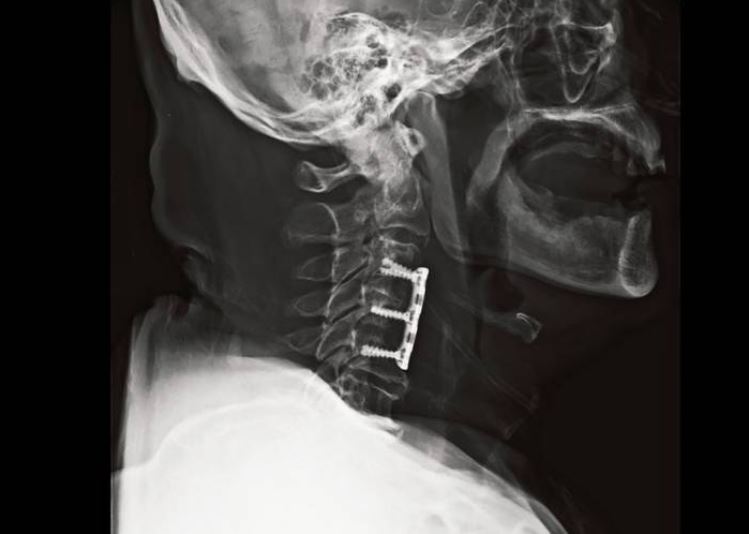

경추 유합술(고정술)

만약 돌출된 추간판이 척수 신경에 압박을 가한다면 전신에 통증, 저림, 마비 증상을 유발할 가능성이 있습니다. 이런 경우는 경추를 금속으로 고정시켜 신경 침범을 예방하고, 경추의 안정성을 높이는 유합술을 시행합니다.(아래 사진 참조)